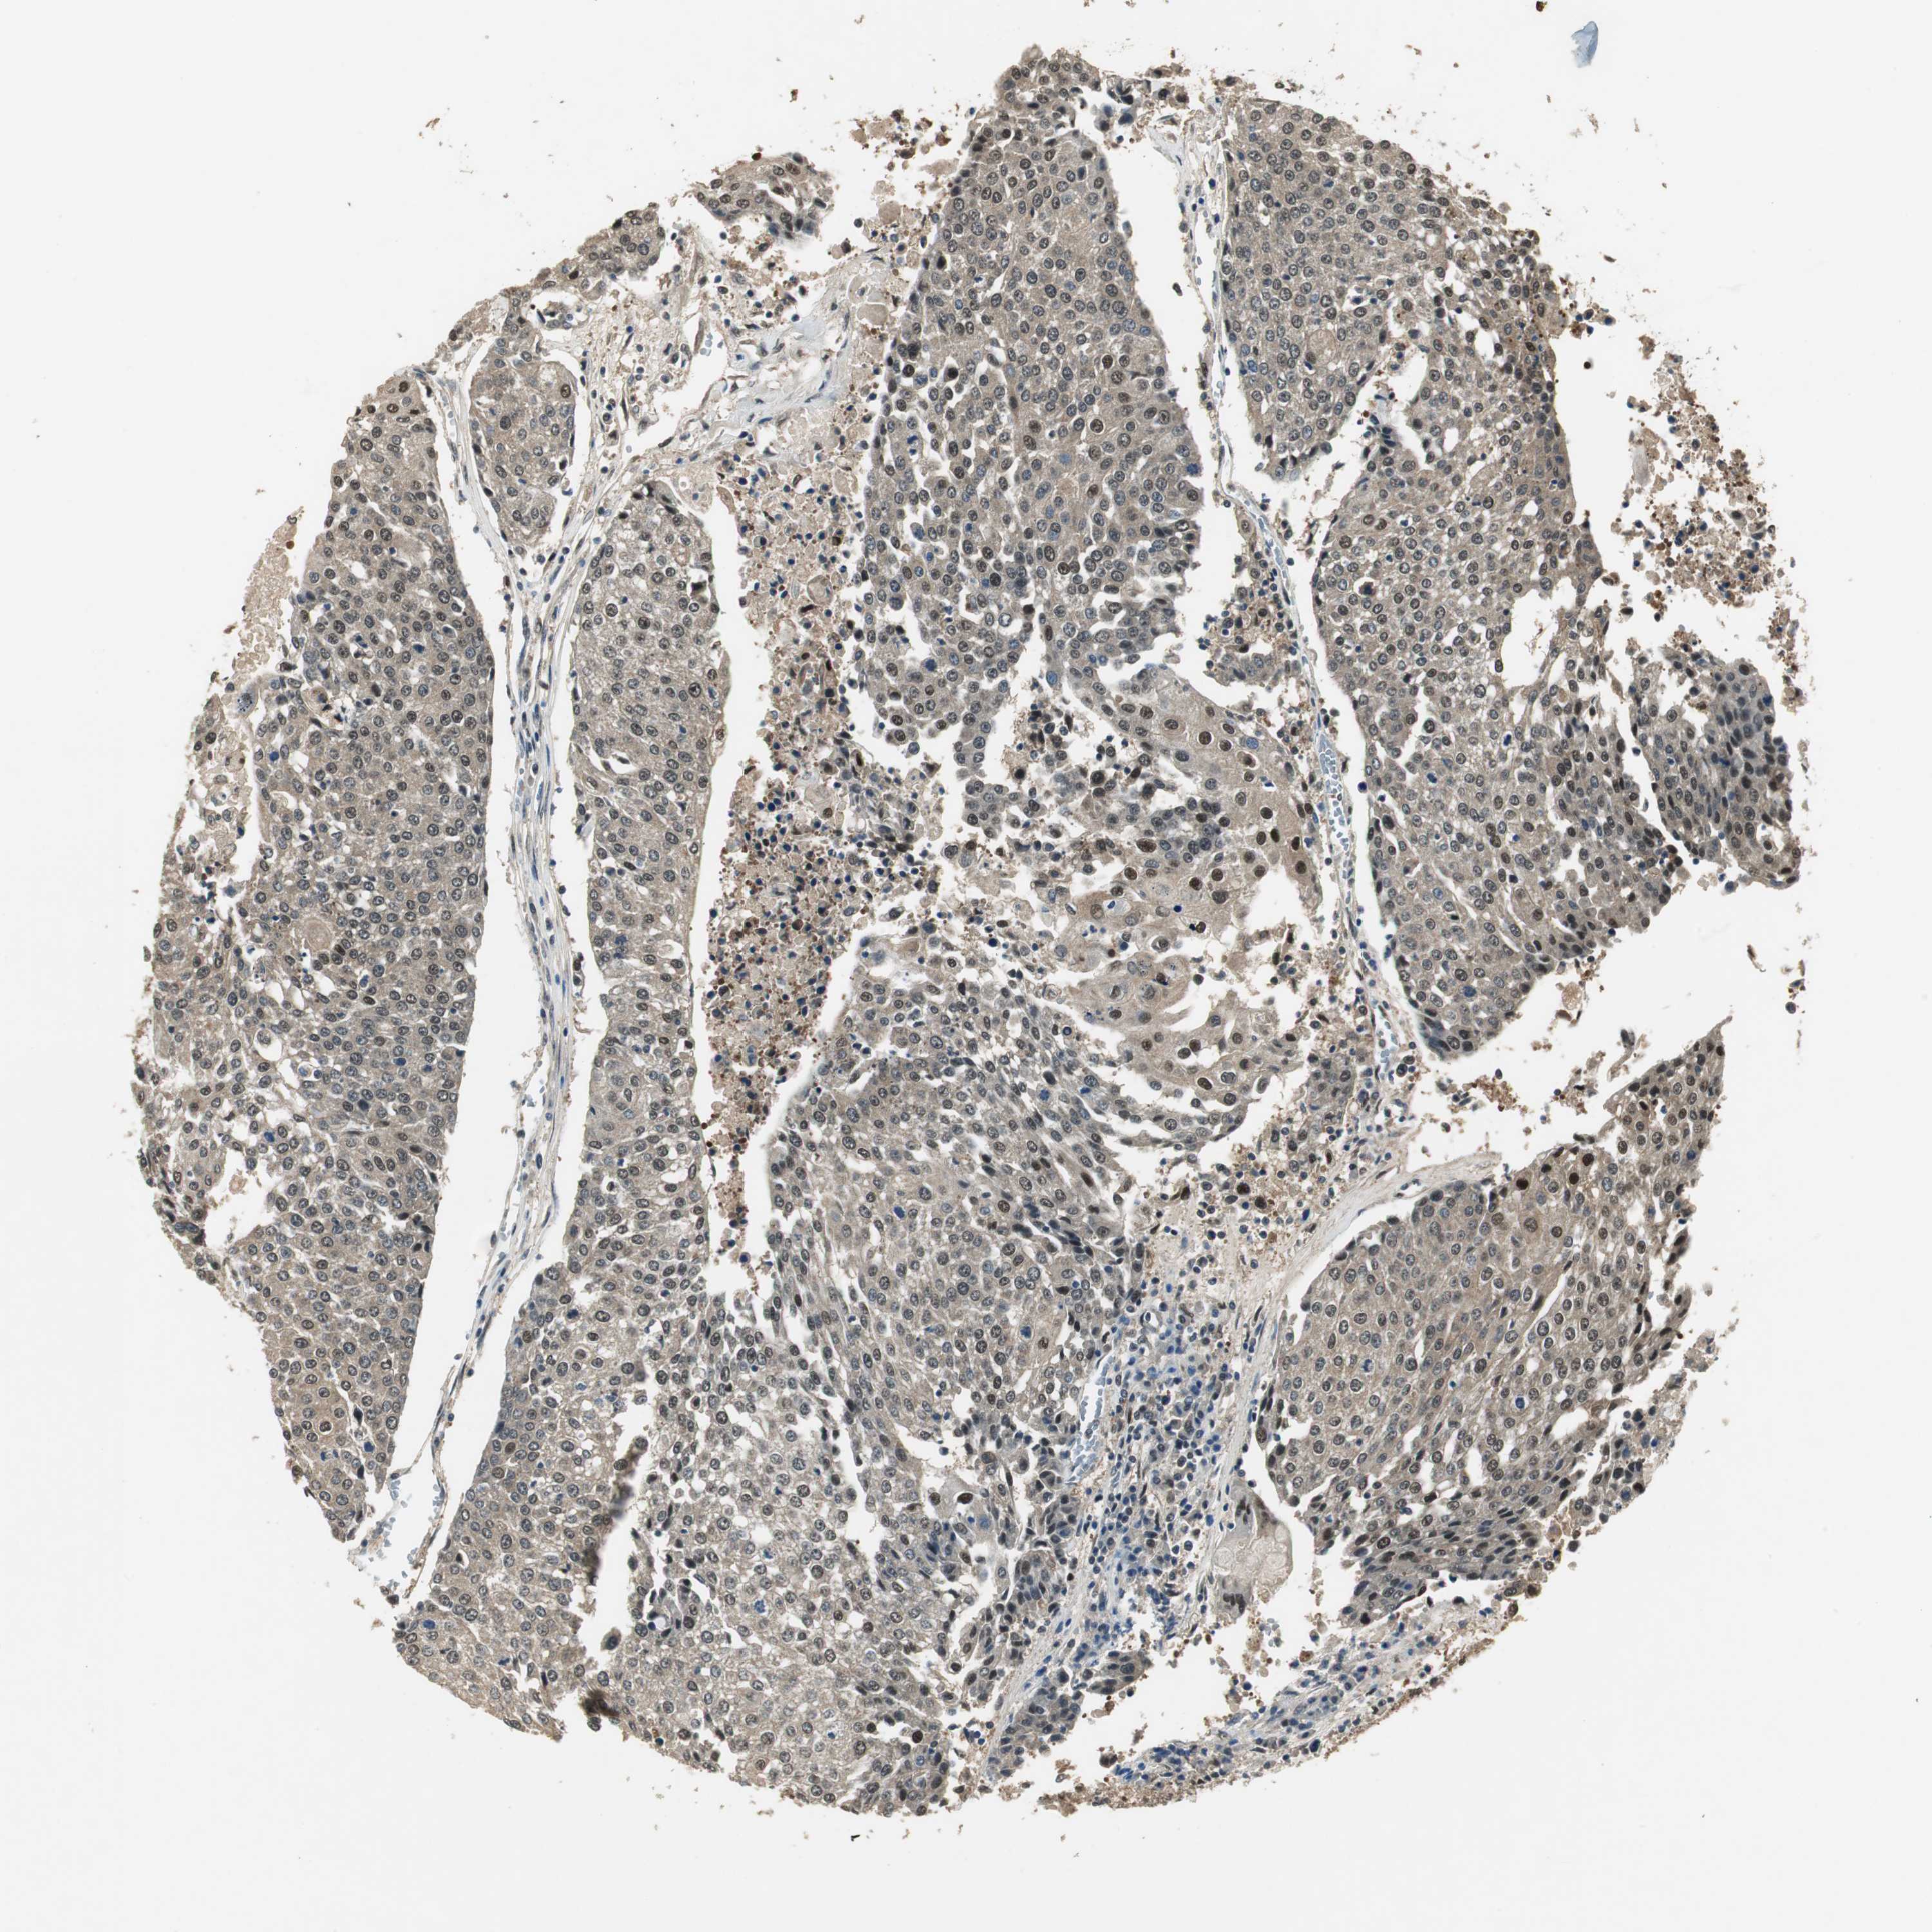

UROTHELIAL CANCER - Protein expressioni

A mouse-over function shows sample information and annotation data. Click on an image to view it in a full screen mode. Samples can be filtered based on level of antibody staining by selecting one or several of the following categories: high, medium, low and not detected. The assay and annotation is described here.

Note that samples used for immunohistochemistry by the Human Protein Atlas do not correspond to samples in the TCGA dataset.

Antibody stainingi

Antibody staining in the annotated cell types in the current human tissue is reported as not detected, low, medium, or high, based on conventional immunohistochemistry profiling in selected tissues. This score is based on the combination of the staining intensity and fraction of stained cells.

Each image is clickable and will lead to virtual microscopy that enables deeper exploration of all samples and also displays staining intensity scores, fraction scores and subcellular localization as well as patient and tissue information for each sample.

Antibody HPA006700

Staining

High

Medium

Low

Not detected

Intensity

Strong

Moderate

Weak

Negative

Quantity

>75%

75%-25%

<25%

None

Location

Nuclear

Cytoplasmic/membranous

Cytoplasmic/membranous,nuclear

Urothelial carcinoma, Low grade

Urothelial carcinoma, High grade